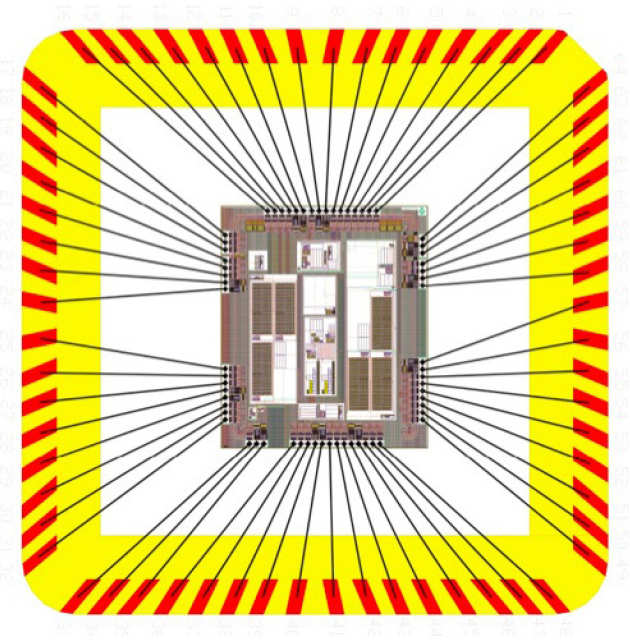

We are developing a new generation of neural interface to provide an innovative treatment for people who suffer from overweight and obesity.

We are developing a new generation of neural interface to provide an innovative treatment for people who suffer from overweight and obesity.

The i2MOVE is about multidisciplinary research. The laboratories of lead experts Professor Chris Toumazou and Professor Sir Steve Bloom have joined efforts to tackle obesity through state-of-the-art neural interfaces.

The i2MOVE is about multidisciplinary research. The laboratories of lead experts Professor Chris Toumazou and Professor Sir Steve Bloom have joined efforts to tackle obesity through state-of-the-art neural interfaces.

The aim is to use obesity as a paradigm to develop the next generation of neural interfaces.